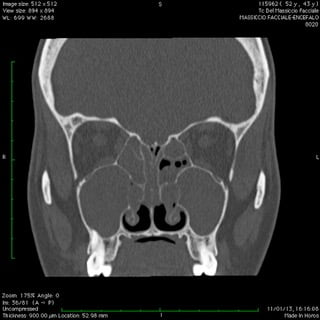

Anche nelle sinusiti la peculiare morfologia anatomica delle strutture coinvolte, cavità ossee, consente nella maggior parte dei casi latenze di esordio molto ritardate rispetto il primitivo insorgere patologico palesandosi così in avanzate fasi di compromissione .

Nelle forme croniche, cioè di malattia stabile nel tempo, i seni paranasali diventano “ siti di decantazione”, ovvero di ristagno e moltiplicazione,per germi di vario genere dando vita così ad un persistente primario serbatoio contaminante sia le vie aeree che quelle digestive.